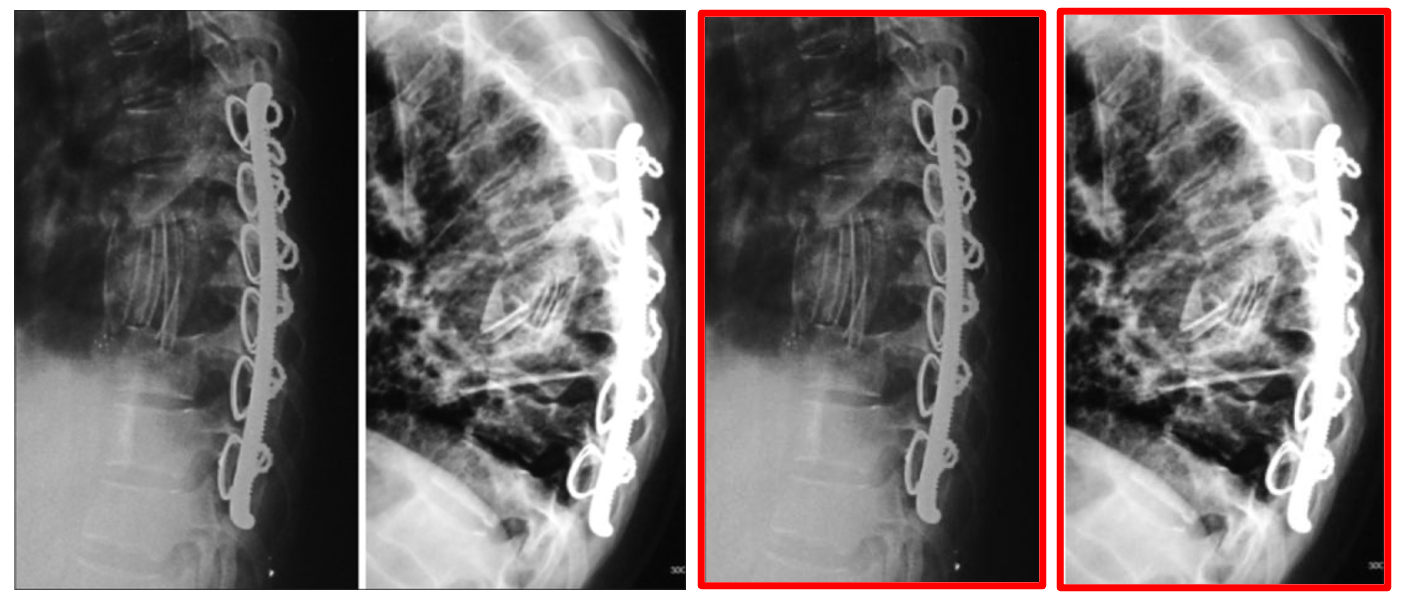

3.4 Cross-Modal Interleaved Samples

A key advantage of MedicalNarratives is its interleaved multi-modal nature. This manifests in two ways: (1) Video-based interleaving: Medical pedagogy videos frequently present multiple imaging modalities for the same patient. Instructors naturally explain relationships between these modalities in a single narrative, creating one-to-many mappings between textual descriptions and images. This allows our model to learn connections between modalities through shared textual context (see Figure 9 in Appendix). (2) Sample-based interleaving: Articles and Videos often contain images with multiple sub-images showing different modalities accompanied by a unified caption. This structure similarly reinforces cross-modal relationships. (see MRI example in Figure 1 and Figure 9 in the appendix). This interleaved nature of MedicalNarratives significantly enhances cross-modal retrieval capabilities, as shown in Sec. 4.4. We open-source our dataset with modality tags which can be used to identify cross-modal samples.